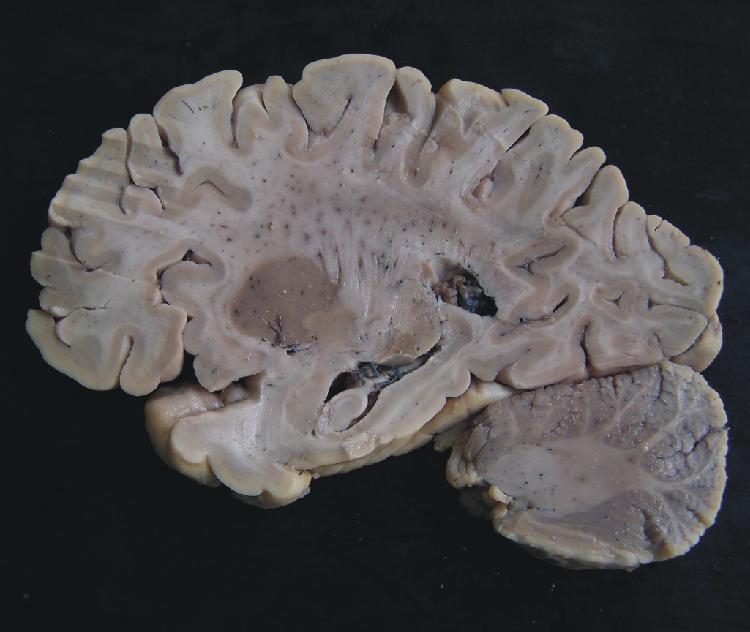

| Sulcus centralis |

| Insula |

| Claustrum |

| Putamen |

| Globus pallidus |

| Nucleus caudatus - corpus |

| Nucleus caudatus - cauda |

| Capsula externa |

| Capsula extrema |

| Ventriculus lateralis - pars centralis |

| Ventriculus lateralis - cornu temporale |

| Plexus choroideus |

| Hippocampus |

| Corpus amygdaloideum |

| Fimbria hippocampi |

| Cerebellum |